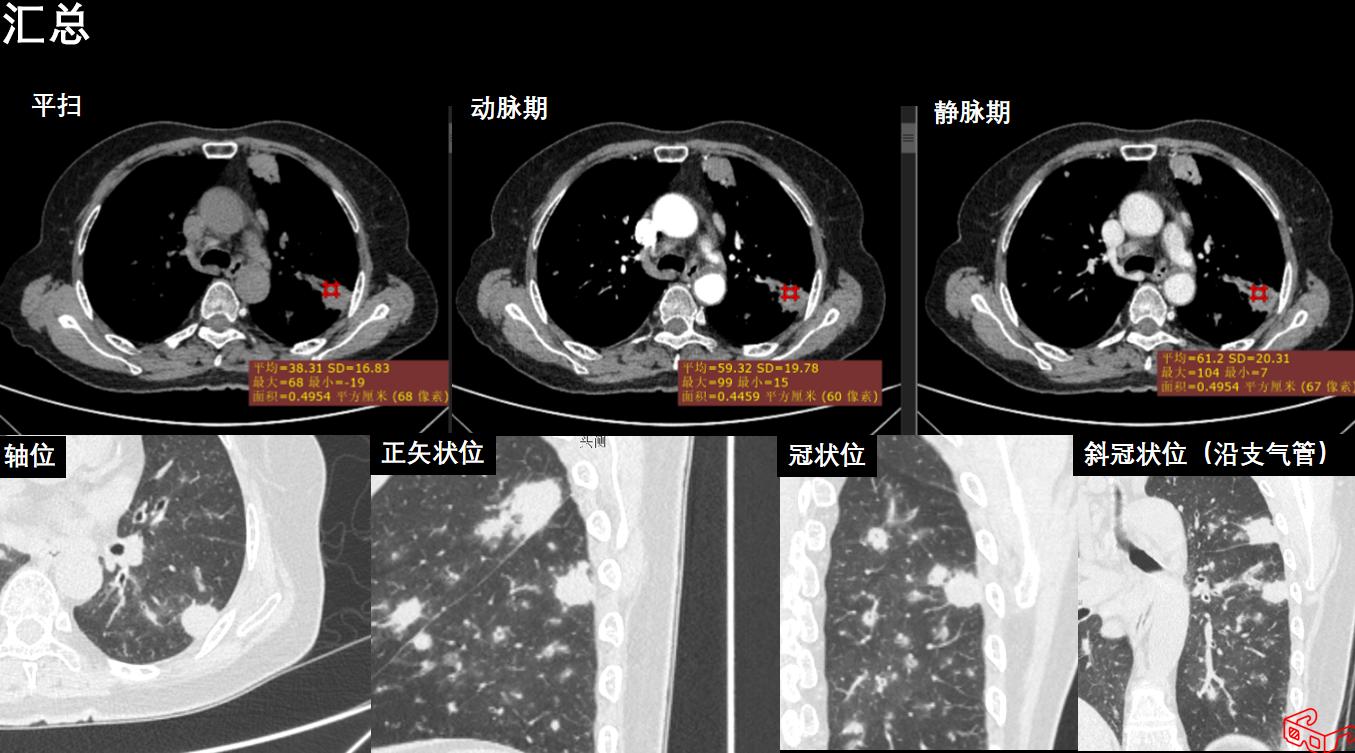

图像:

影像描述:双肺多发结节状密度增高灶,周围可见晕征、毛刺、胸膜牵拉征象,可见空洞样改变,内壁光整,增强轻中度强化,未见淋巴结肿大和胸腔积液。

影像诊断:双肺多发病变(1.真菌感染?2.肺癌?)

病理:肉芽肿性炎。经规范激素+免疫调节治疗后复查,双肺病变明显缩小。